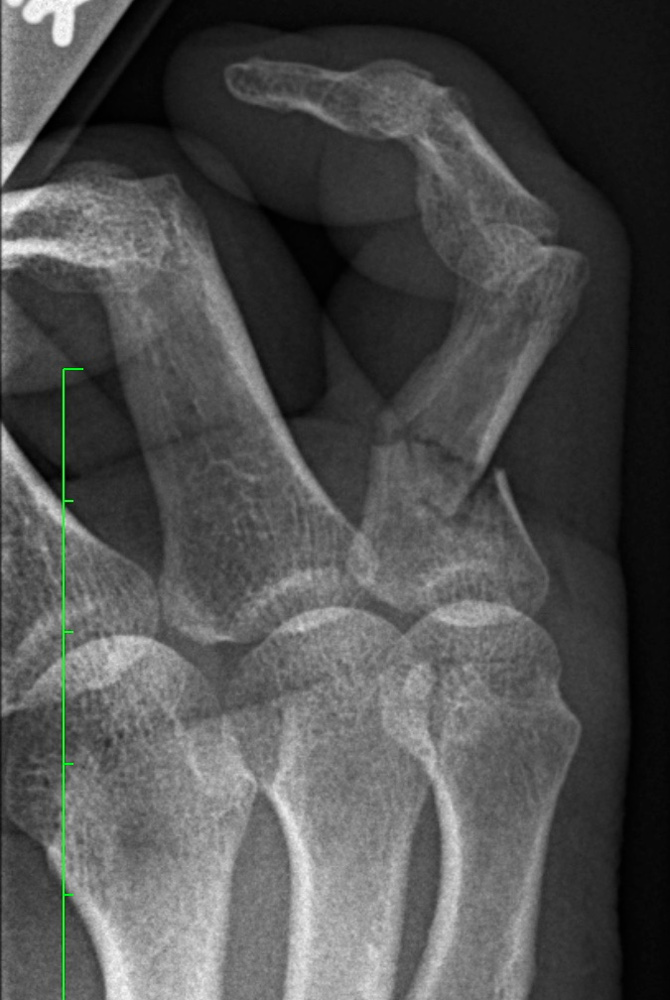

I broke my pinky on March 28, 2019 while doing an end sprint along the river houses near Dunster house. There is a dominant lonely tree there with a square shape root, hence square root over I fell over. The pinky was indeed in a terrible shape. Some nerve also got stuck because it did not hurt. But it looked not good. The technical description of the doctor was "continued angulated intra-articular fracture of the proximal phalanx of the 5th finger" It is true that I was referred to Mt Auburn Emergency. It is also true that I got charged again 30 dollars co-payment, but there was fortunately a lovely lady there whom I could convince that I already payed my 30 dollars before at HUHS (lovingly called Huuuuuhhh!s by the students). I indeed had met a cook there who told me that he had bled there for 3 hours. At the hospital, they indeed could already rectify a bit of the finger as otherwise, I would not have fit into the splint. It is true that each surgeon visit was again 30 dollars co-payment. I had to cut short the first appointment myself as I had a teaching commitment later. You can not assume that a doctor visit takes only 90 minutes. During the second visit, the pinky was linearized. The hand surgeon did it without actually needing to cut, it was a bit like molding (of course with a completely numbed up hand). He could not have done it better. No, nobody ever said "that is fucked up". The language of doctors is much more sophisticated (as you can see in the report of my doctor):